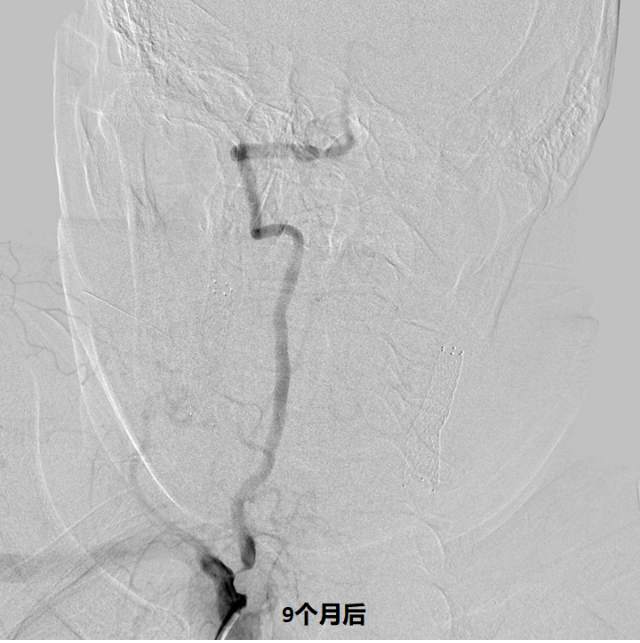

和家属商量后,我们采用全球首款椎动脉专用药物洗脱支架(Maurora)成功精准切线位植入,消除了这个“卡脖子”的狭窄……

术后随访结果:老人家说话口齿清晰了,思维反应也快了……